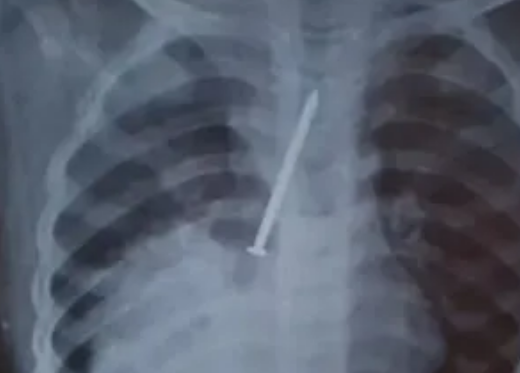

Um menino, de apenas 3 anos, morreu após ter o pulmão perfurado por um prego, em Canasvieiras, no Sul do Estado da Bahia. A família acredita que a criança estivesse com o objeto no corpo há um ano e acusa a equipe médica de negligência por não ter pedido exames básicos para o diagnóstico correto. O caso aconteceu, na última sexta-feira (1º), mas foi publicado apenas nesta quinta-feira (7).

Os pais levaram o menino para unidade de saúde várias vezes, mas só descobriram que ele tinha ingerido o prego quando resolveram fazer um exame por conta própria, pela rede particular. A criança começou a tossir com frequência e apresentar febre, no último dia 27, quando os pais procuraram o hospital novamente.

A Secretaria Municipal de Saúde de Canavieiras informou que na data, foram solicitados exames e uma consulta foi marcada com um pediatra para o dia seguinte, mas médico ficou doente e não houve atendimento. A mãe de Cauan realizou o raio-x solicitado pela médica durante a primeira consulta. O exame comprovou que a criança engoliu um prego de 10 centímetros. O garoto morreu na sexta-feira passada (1º) e foi enterrado no sábado (2).